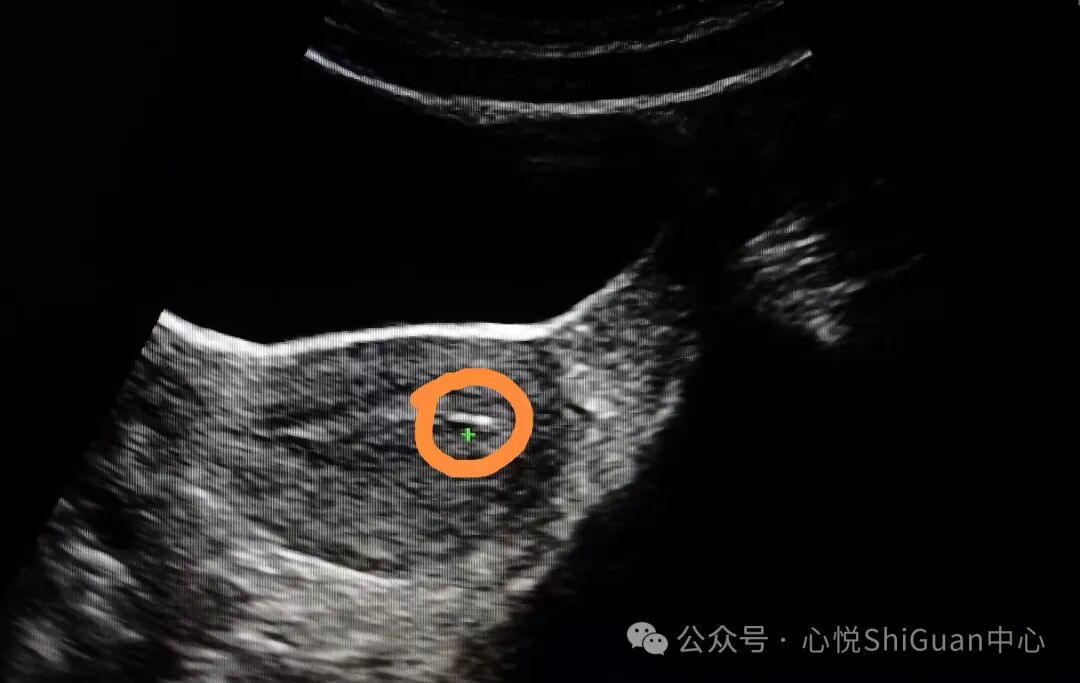

2.评估子宫内环境:

通过B超检查,可以观察子宫内膜的厚度和质地,这些都是评估子宫是否适合胚胎植入的重要因素。